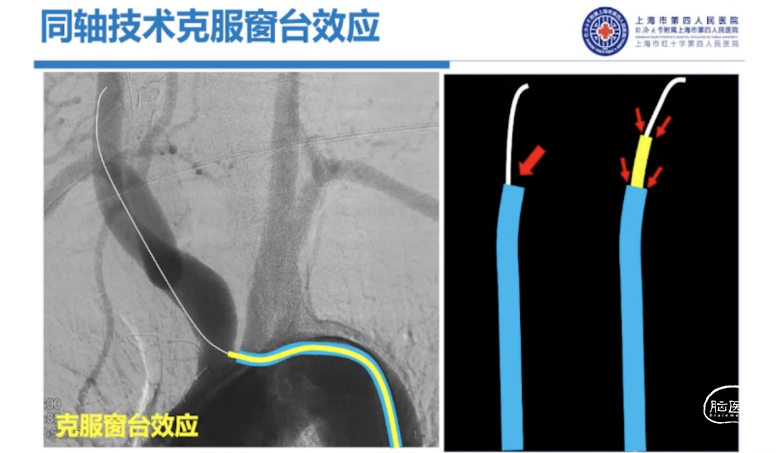

早期同轴技术的应用:在使用粗导管过弓时使用同轴技术来克服窗台效应,减少局部块脱落,增加导管通过的成功率。

过往的同轴技术是柔软内芯+相对支撑良好的外管,而R-DAS技术恰恰相反,是硬内芯(支撑)+软外管(建立通路)的组合。